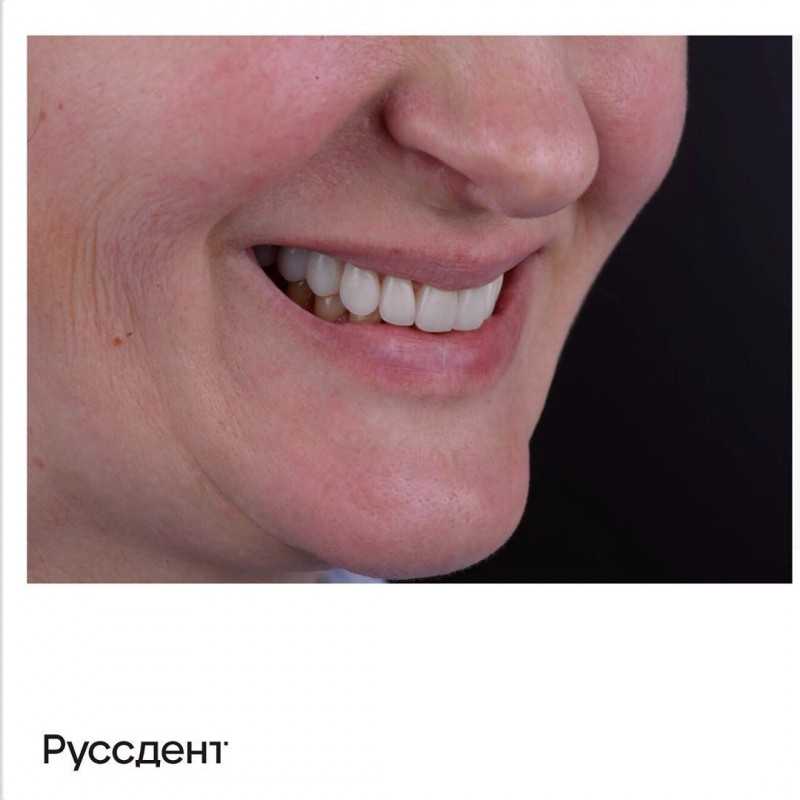

23 работы в портфолио

Главный врач Рамазанов Руслан Керимович принимает в Стоматологии NEW DENT (НЬЮ ДЕНТ) в Краснодаре. Имеет рабочий стаж 8 лет. Специализируется на ортопедии, по которой клиника оказывает 11 услуг. Имеет 23 работы до/после в портфолио. Квалификация специалиста подтверждена 19 лицензиями, сертификатами и наградами. Для уточнения дополнительной информации о специалисте или записи на прием можно позвонить по телефону